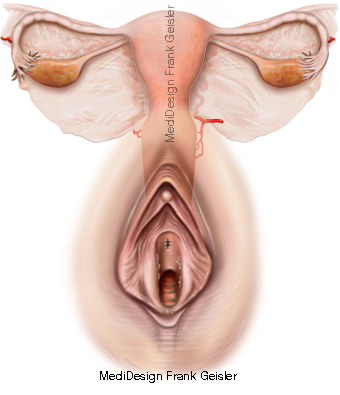

Geschlechtsorgane der Frau

Die inneren weiblichen Geschlechtsorgane sind Eierstock (Ovarium), Eileiter (Tuba uterina), Gebärmutter (Uterus) und Scheide (Vagina), die sich alle im Beckenbereich befinden. Die äußeren weiblichen Genitalorgane bestehen aus den großen Schamlippen (Labia majora), dem Kitzler (Clitoris), den kleinen Schamlippen (Labia minora), dem von ihnen eingeschlossenen Scheidenvorhof (Vestibulum vaginae) mit den hier mündenden Drüsen und der äußeren Öffnung der weiblichen Harnröhre (Urethra). Vulva (Pudendum femininum) bezeichnet die Gesamtheit der äußeren Geschlechtsorgane einer Frau.

Schnittdarstellung Scheide und Gebärmutter mit Eileiter und Eierstöcke, Eireifung und Follikelsprung; Vulva erregt mit Kitzler und Uterus; Klitoris, ein aus Schwellkörpergewebe bestehendes Lustorgan der Frau

Geschlechtsorgane Gebärmutter Scheide Vulva der Frau; Uterus mit Eileiter Eierstock und Vagina

Der (Klitoris, Clitoris) der Frau ist ein aus Schwellkörpergewebe gebildeter Teil des weiblichen Genitals, der weiblichen Scham, das entwicklungsgeschichtlich dem Penis des Mannes entspricht. Die Klitoris ist ein erektiles Organ am oberen Ende der kleinen Schamlippen (Labia minora pudendi).

Das äußere Genitale beginnt in Höhe der Symphyse mit dem oberhalb der Schamspalte (Rima pudendi) liegenden Schamberg (Mons pubis). Nach unten und seitlich folgen die großen Schamlippen. Innen begrenzen die kleinen Schamlippen mit ihrer Innenfläche den Scheidenvorhof. Hier mündet wenig unterhalb der Klitoris (Kitzler) die weibliche Harnröhre in den Scheidenvorhof.